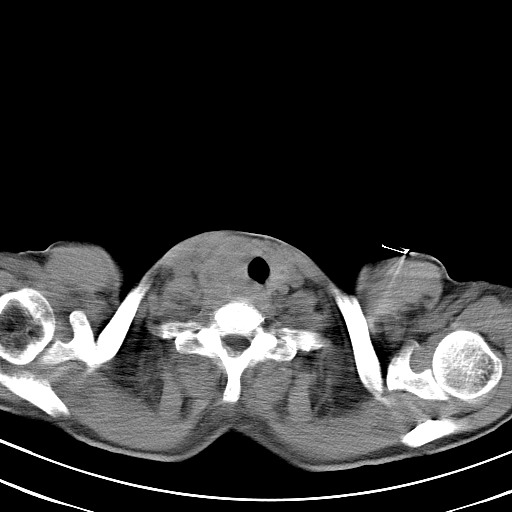

以下是引用汪涛同志在2007-8-2 0:40:00的发言:[br]病变虽然广泛,同时侵及双侧纵隔,但是无论左侧和右侧上下观察都是与右侧颈部甲状腺相延续的,而且强化幅度基本一致,又同时具有恶性病变病变的某些特征:肿块过大且密度不均,部分层面与正常纵隔结构分界不清,结合病史已有两年,考虑:胸内甲状腺肿恶变可能。[br]